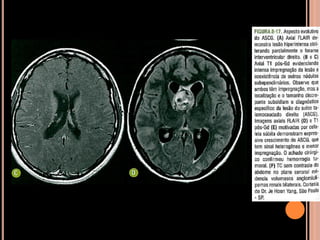

 ENCÉFALO

Túberes corticais;

Nódulos subependimários;

Astrocitoma subependimário de células

gigantes(ASCG);

Lesões de substância branca por distúrbios de

migração neuronal;

Achados de imagem

CET

Achados de imagem – Ressonância magnética

 Recomendações

RM: método de escolha;

anual em paciente com CET e nódulos

subependimários adjacentes ao forame de Monro,

parcialmente calcificados e com impregnação pelo

Gd (crescimento e obstrução)  favorece ASCG e

indica cirurgia precoce;

TC sem contraste: só para ver nódulos

subependimários calcificados;